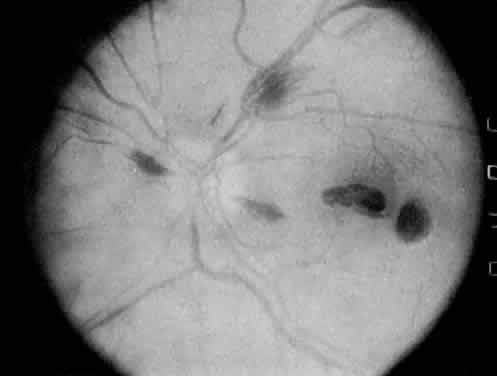

The classic ocular finding in DIC is serous retinal detachment64,65 (Fig. 5). The pathogenesis of these detachments involves choriocapillaris occlusion resulting in retinal pigment epithelial damage and subsequent loss of retinal pigment epithelial barrier and pump function. Fluorescein angiography confirms this pathophysiology, showing delayed filling of the posterior choroid with later pigment epithelial staining (Fig. 6). If the underlying DIC can be reversed, the retina may reattach, with return of vision. Other findings associated with DIC include retinal and vitreous hemorrhages.

Fig. 5. Serous retinal detachment in disseminated intravascular coagulation. (Hoines J, Buettner H: Ocular complications of disseminated intravascular coagulation [DIC] in abruptio placentae. Retina 9:107, 1989.)

Fig. 6. Delayed choroidal filling with pigment epithelial staining in disseminated intravascular coagulation. (Hoines J, Buettner H: Ocular complications of disseminated intravascular coagulation [DIC] in abruptio placentae. Retina 9:107, 1989.)